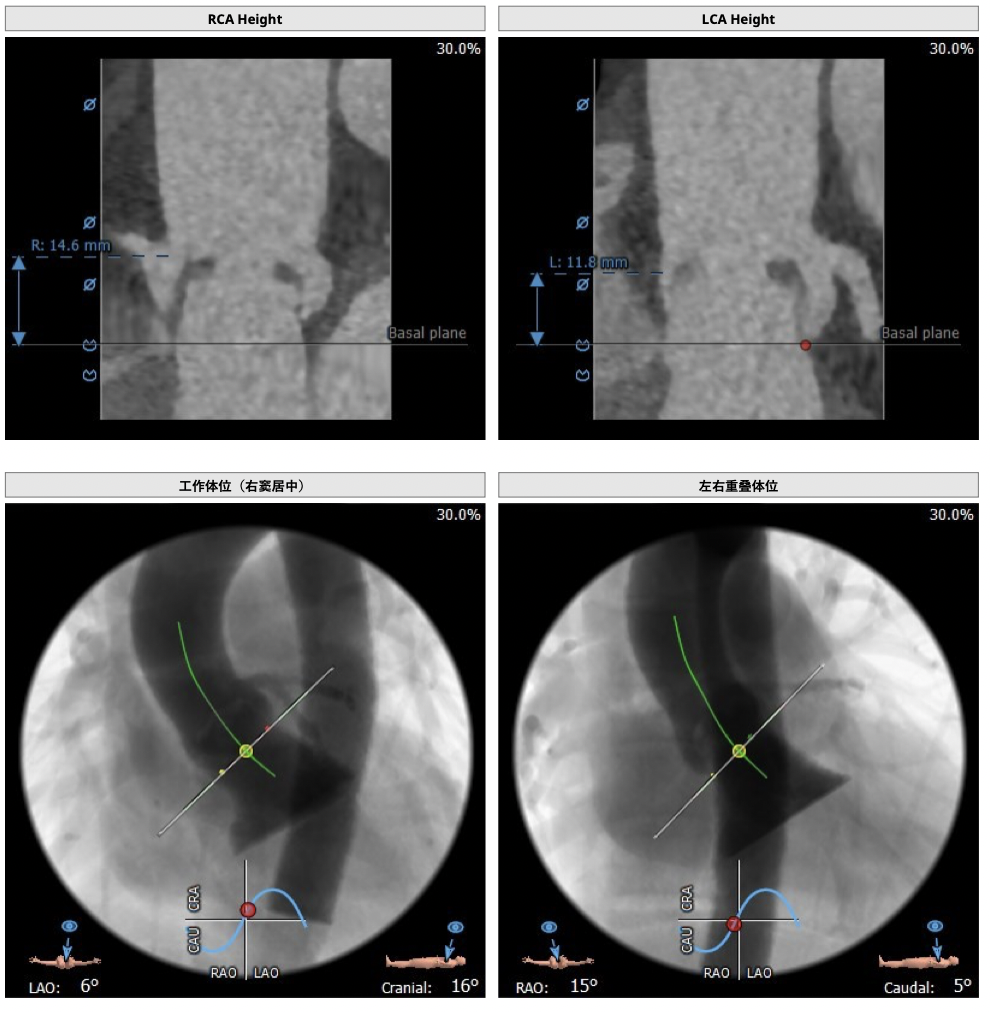

CT检查

③左冠高度不高,且瓣叶冗长,达冠脉开口层面,且冠脉存在狭窄,存在冠脉阻塞的风险;

制定策略

确保冠脉安全,拟采取PCI+TAVR一站式手术策略,因患者右侧股动脉钙化严重、入路狭窄,拟采取无鞘法从右股动脉穿刺入路,选用20mm球囊预扩、L23号VenusA-Valve瓣膜、采用VenusA-Plus输送系统确保瓣膜的精确释放,瓣膜释放后结合造影和超声情况,决定是否后扩。